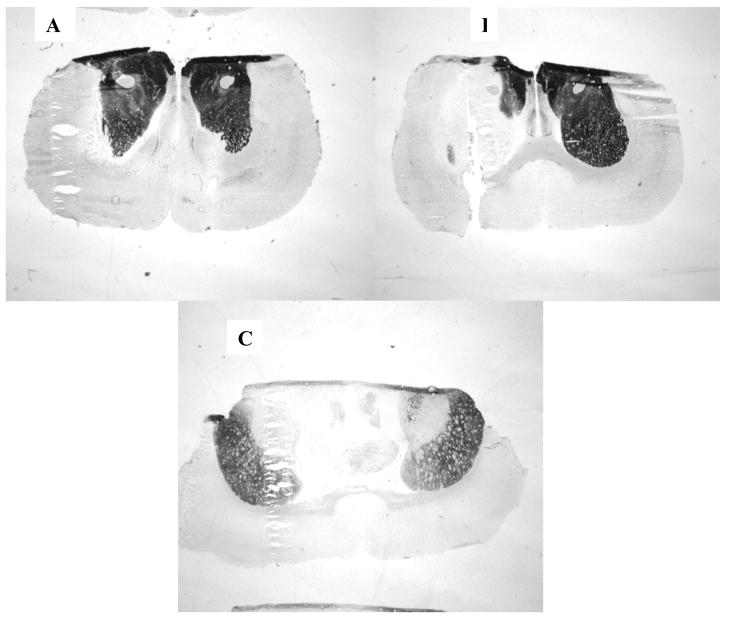

Histochemistry of brain sections revealed the distribution of AChE activity after infusion of vehicle (aCSF), or paraoxon (1 or 3 mM). After aCSF infusions, AChE staining in ipsilateral and contralateral striatum was comparably intense (Figure 3A). After infusions with 1 mM paraoxon, however (Figure 3B), most of the ipsilateral striatum lost all staining, while the contralateral side was largely unaffected. In contrast, after infusion of 3 mM paraoxon, there was marked reduction in staining on both sides. Thus, the biochemical and histochemical assays generally agreed in demonstrating unilateral ChE inhibition from paraoxon infusions at I mM, but bilateral inhibition at 3 mM.

Figure 3. Histochemical analysis of acetylcholinesterase inhibition following paraoxon infusion.

A) AChE staining in rats infused with aCSF, B) AChE staining in rats infused with 1 mM paraoxon, and C) AChE staining in rats infused with 3 mM paraoxon. In all panels, the cannulated (ipsilateral) side is on the left. Within each treatment condition, replicate animals (n=3/treatment group) showed the representative pattern of AChE staining.